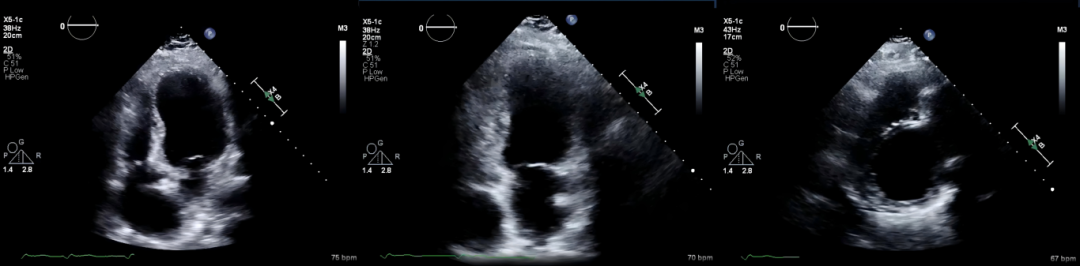

病例简介患者,男性,76 岁。主诉:因急性上腹痛、腹胀伴有呕吐和便秘3天,到急诊科就诊。关键病史:既往有胰腺癌病史,曾接受过胰十二指肠切除术(Whipple 手术)。查体示:腹部检查显示弥漫性压痛,无肌紧张。影像学发现:床旁超声(图 1)。计算机断层扫描(CT)(图2)。图 1 上腹部床旁超声图 2 CT成像显示(A)横断面和(B)矢状面你的诊断是什么?后续如何干预?(评论区说说你的看法)